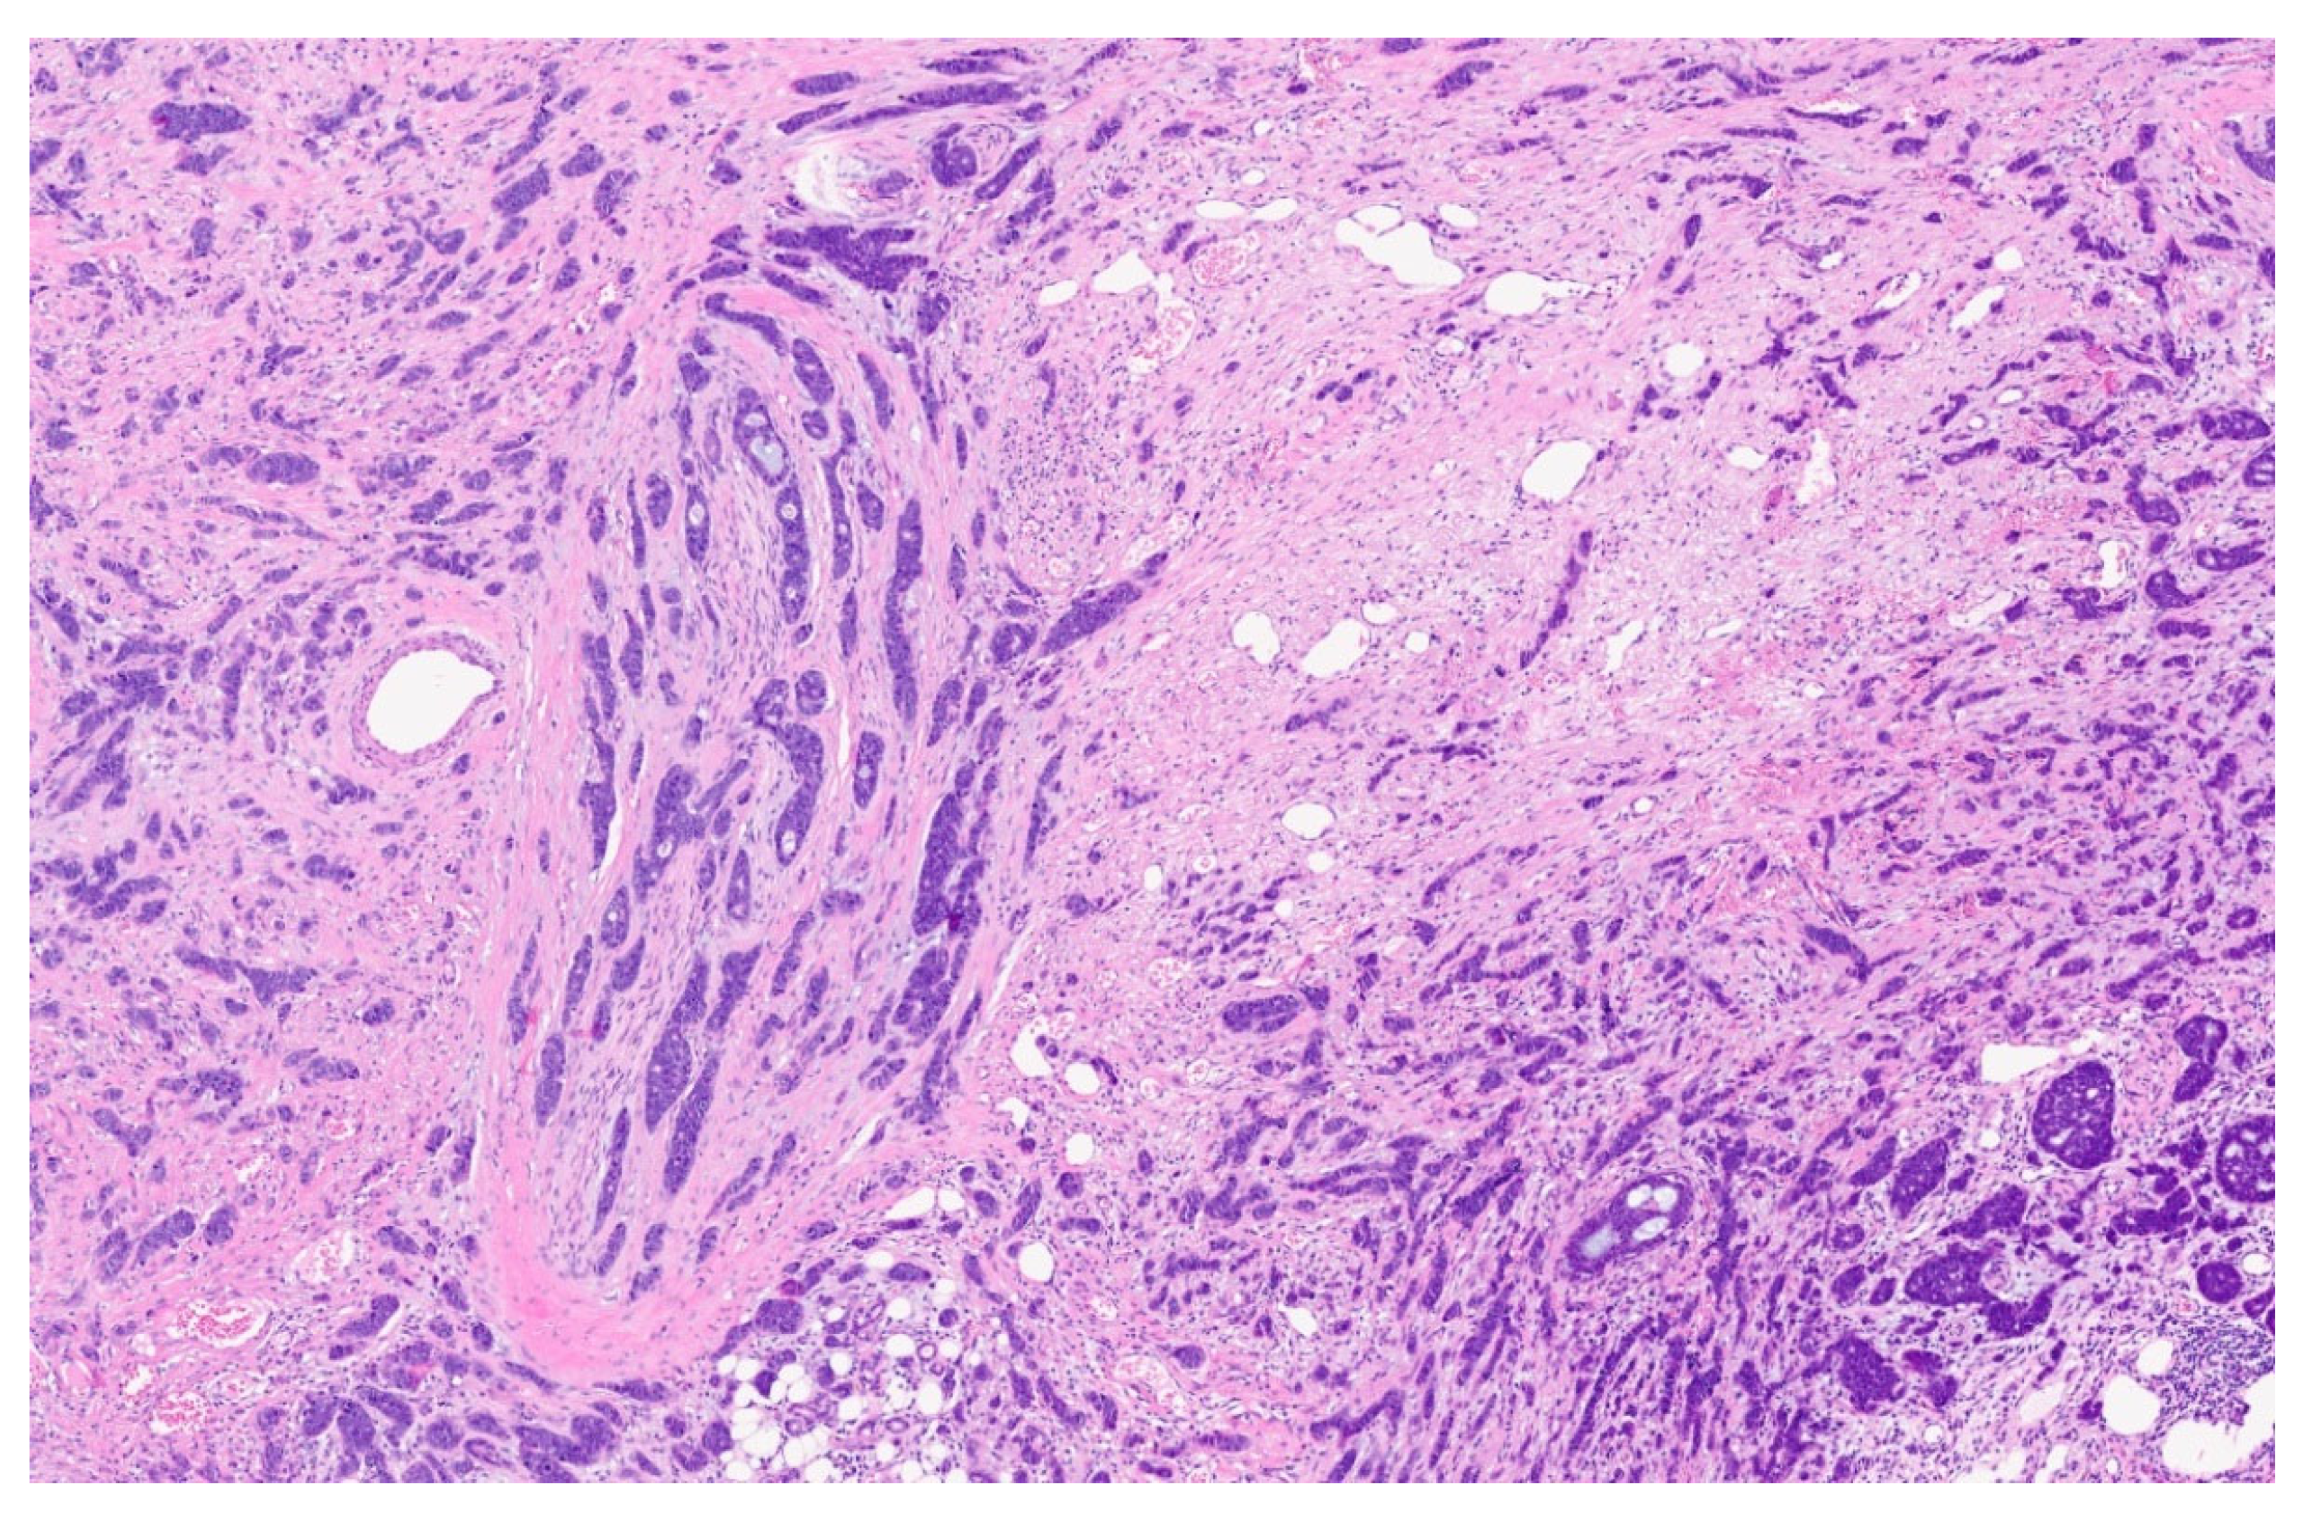

2. Case Presentation